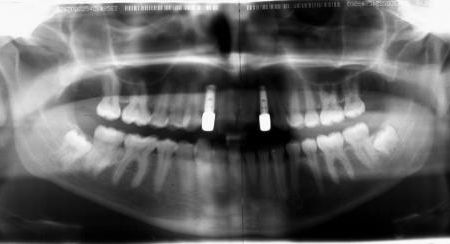

Während der Behandlung

Die Backenzähne wurden mit einer im Gaumenbereich angebrachten, festsitzenden Apparatur zunächst nach hinten bewegt, bis die Verzahnung richtig eingestellt war. Dies war nach ca. 1 Jahr erreicht. Anschließend wurde die Bracketspange eingesetzt. Der Aufbau des rechten Eckzahns wurde entfernt, die Lücken mit über den umlaufenden Drahtbogen gestreiften Spiralfedern geöffnet und dabei auch die obere Zahnbogenmitte eingestellt (linkes Bild). Die feste Zahnspange wurde nach 1 Jahr und 4 Monaten zunächst durch eine abnehmare Spange mit Prothesenzähnen zum Ersatz der fehlenden Schneidezähne ersetzt (rechtes Bild).